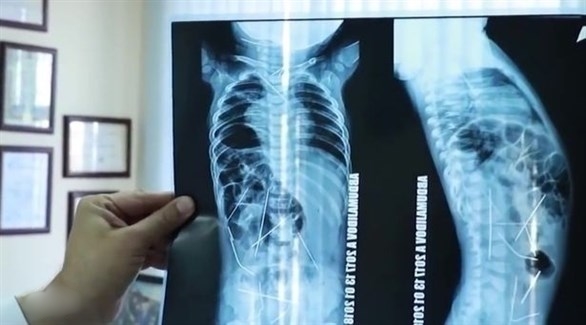

وأظهرت صور الأشعة السينية، وجود 16 إبرة خياطة داخل جسد الطفل، في كل من القلب والعنق والعمود الفقري والقولون والمثانة، وذلك بعد نقله إلى المستشفى، حيث خضع على الفور لعملية جراحية عاجلة استمرت 9 ساعات، تمكن الأطباء فيها من إزالة 13 إبرة.

وخلال العملية الجراحية الدقيقة، أزال الجراحون 3 إبر من صدر الطفل، و9 أخرى من بطنه، وواحده من صدره، وفق ما اوردت شبكة ” 24 ” الإماراتية، ومن المقرر أن يخضع لعملية جراحية أخرى، لإزالة الإبر المتبقية، والتي لا تشكل تهديداً لحياته، بحسب صحيفة ميرور البريطانية.